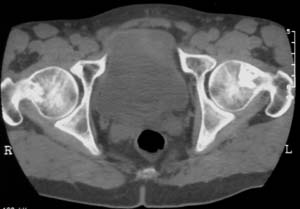

男,61岁,左侧髋关节疼痛,负重后更明显

现上传ct片

左侧股骨头增密,其内见有囊变密度减低区,关节面骨质硬化,关节间隙及髋臼无异示。考虑股骨头缺血坏死可能。建议mri检查。

我觉得股骨头未见到明显的问题,左侧股骨颈有卵圆形高密度影,考虑骨岛或骨梗死。

1\\左侧股骨颈有卵圆形高密度影,考虑骨岛或骨梗死。2\\由于临床症状疼痛,应该mri检查排除早期股骨头缺血坏死

左侧股骨颈处一卵圆形密度增高影,边界清,临近骨组织未见明显破坏.考虑为骨梗死,骨岛?